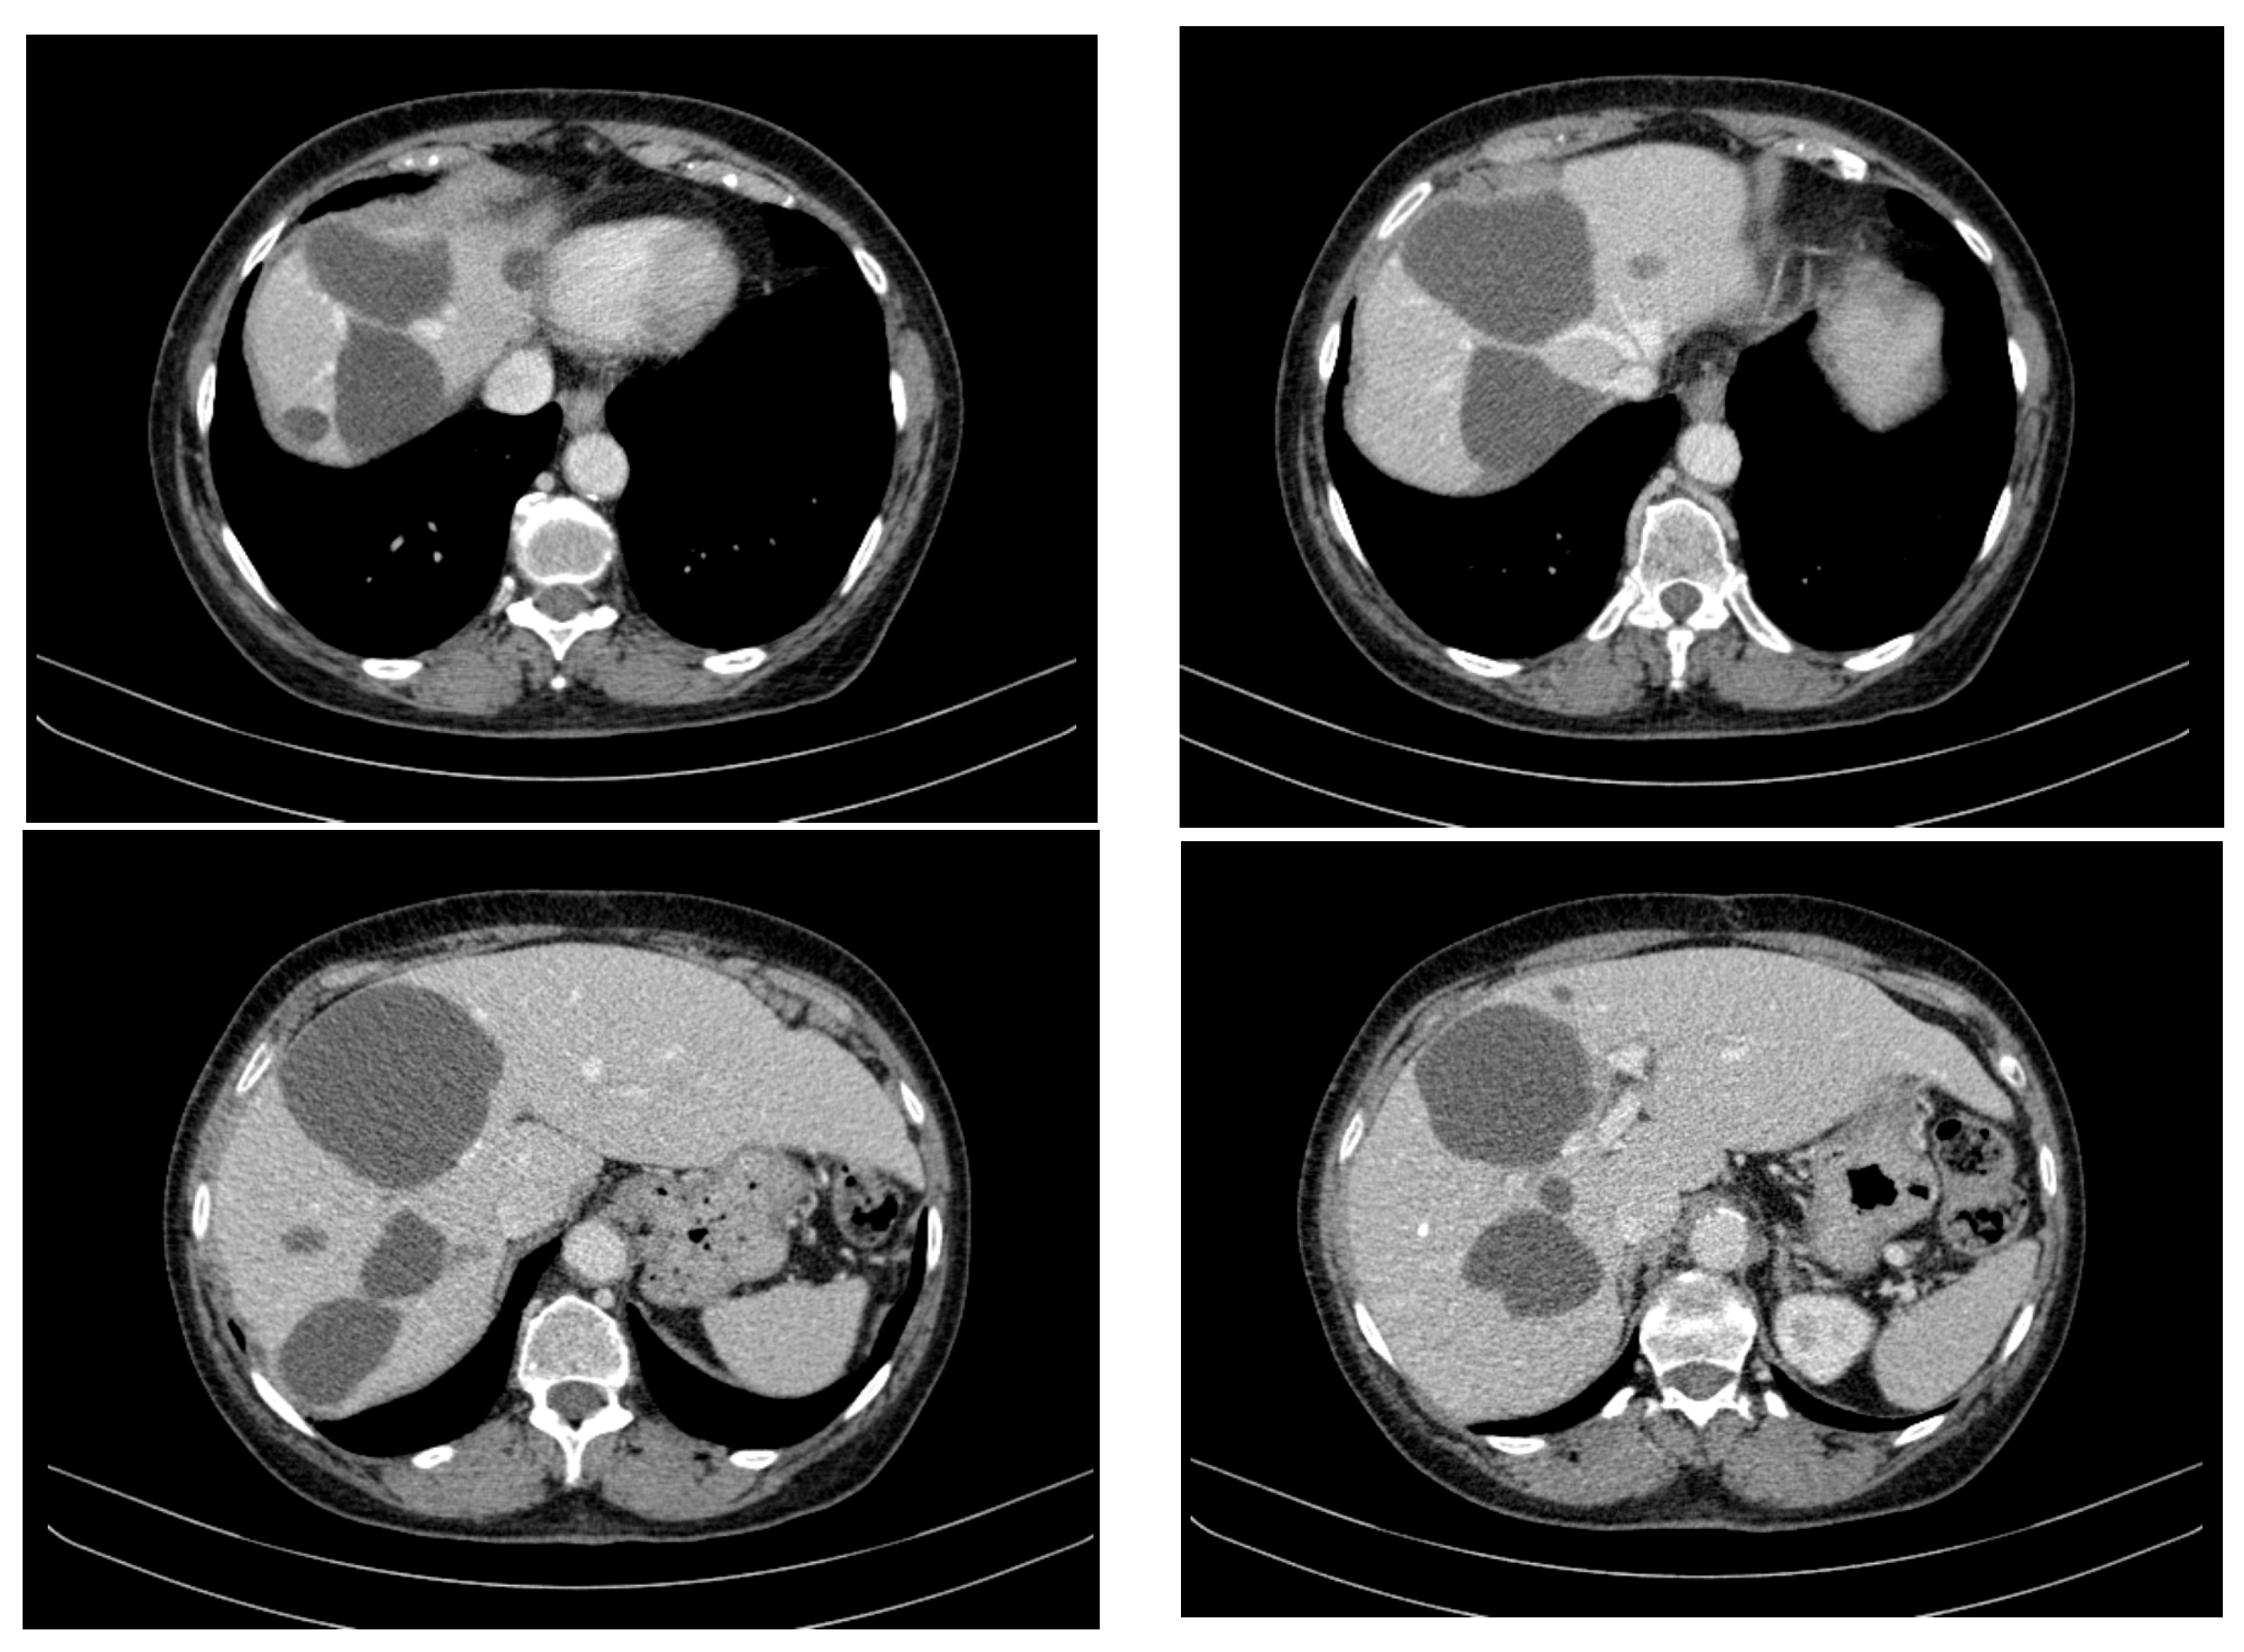

- Large cystic formations: Occupying the right hypochondrium and flank, epigastrium, left hypochondrium, and left flank, with a transonic appearance, thickened heterogeneous wall (up to 3 cm), and irregular hyperechoic septations, some possibly vascularized.

- Largest transonic formation: Located in the left abdomen with a heterogeneous circumferential wall (up to 8.3 in thickness); contained heterogeneous fluid with multiple echogenic/hyperechoic echoes, which were mobile upon compression (Figure 2).

- Hepatic tumour stability: Multiple large cystic hepatic lesions remained stable in size throughout the monitoring period, with no significant new secondary lesions developing. The largest hepatic cystic tumours persisted in segments IV, VI, and VIII, with maximum dimensions of ~8 cm, without major structural changes.

- Imaging: Abdominopelvic CT showed numerous cystic liver lesions (1 cm to 18 cm), mostly in the right hepatic lobe. Largest cysts in segments IVb and III of the left hepatic lobe.